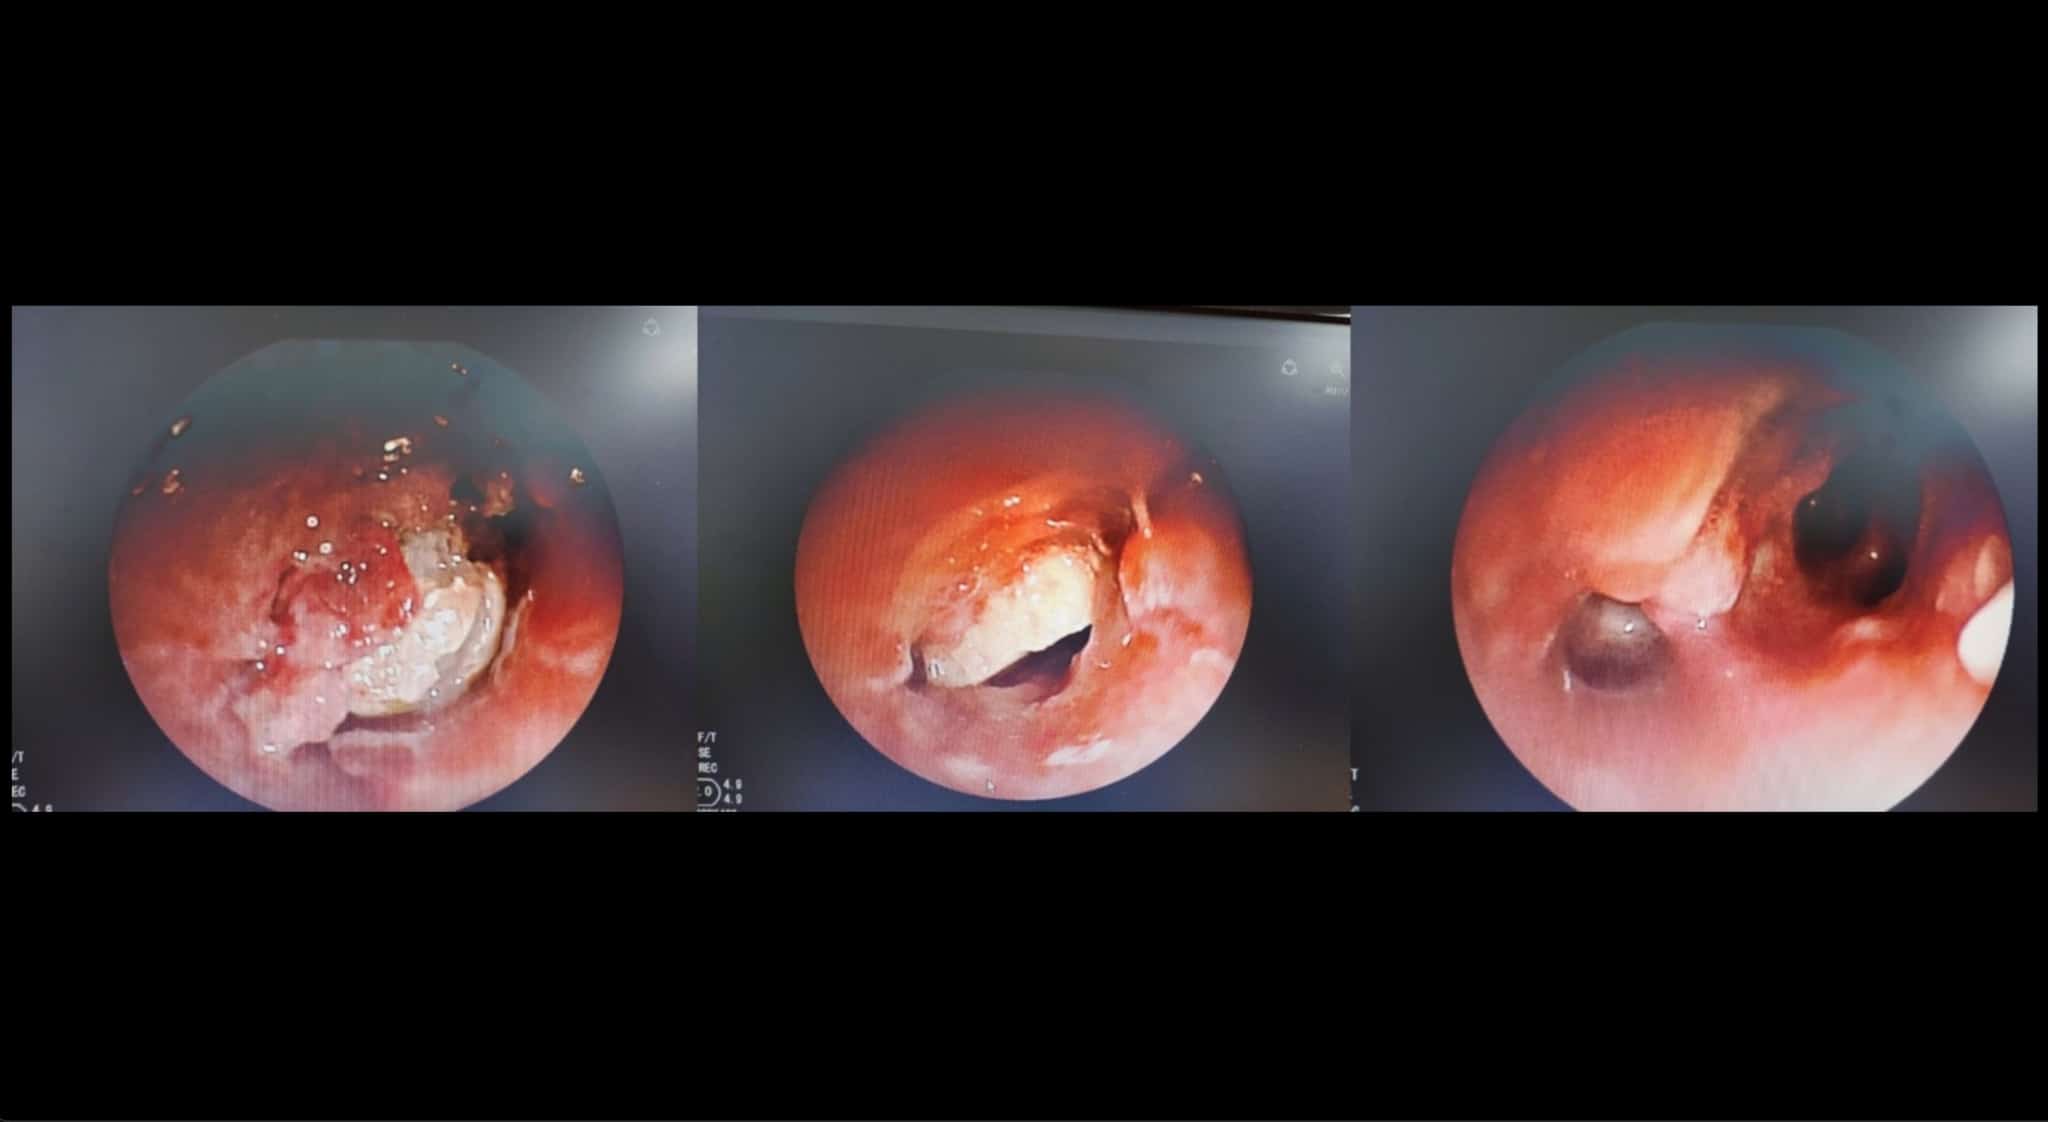

Khi tiến hành nội soi đường thở bằng ống soi mềm qua đường mũi dưới gây mê tĩnh mạch, ê-kíp bác sĩ xác định dị vật là hạt hạnh nhân đã nằm trong phế quản 7 ngày, kích thích phản ứng viêm dữ dội.

Niêm mạc phế quản gốc trái bị sung huyết, xuất hiện mô hạt và giả mạc viêm bao bọc chặt dị vật. Ngoài ra, lòng phế quản còn chứa nhiều đàm trắng đục, làm hạn chế tầm nhìn và gây khó khăn cho việc tiếp cận bằng các dụng cụ nội soi thông thường.

Dựa vào hình ảnh này, các bác sĩ sử dụng thòng lọng tim mạch 3 vòng (Atrieve Snare 4–8 mm) để luồn ra phía sau dị vật. Khi đã ở vị trí thích hợp, thòng lọng được bung ra để giữ chặt hạt hạnh nhân và kéo ra được một phần dị vật.

Phần còn lại sau đó được lấy ra thành công bằng kìm cá sấu hô hấp truyền thống.